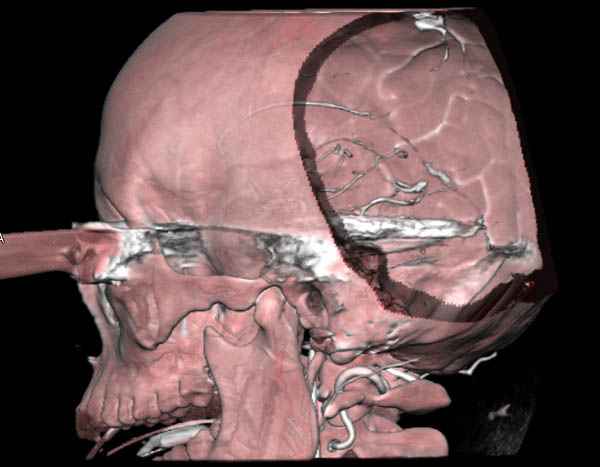

По протоколу сделаны все необходимые исследования: рентген, ангиограмма с 3Д реконструкцией, где обнаружили что все жизненно важные сосуды не задеты, даже некоторые "сидят" изгибаясь на ноже.